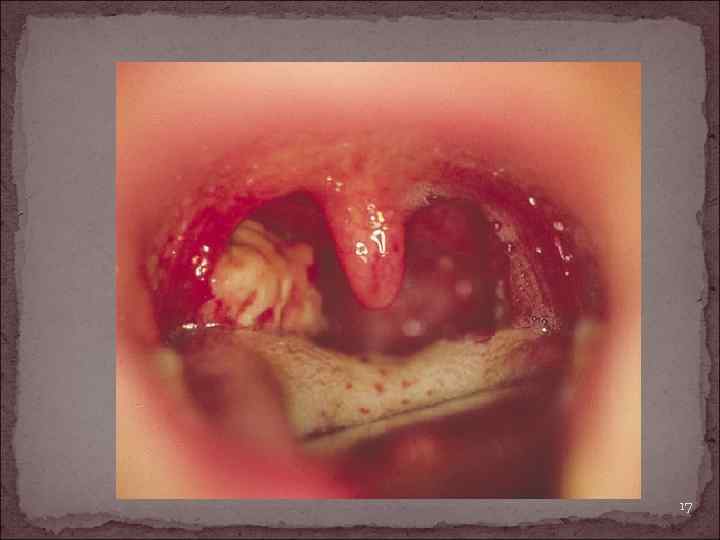

Морфология Из мягкотканных опухолей небной миндалины чаще всего встречаются фибросаркомы и ангиосаркомы. Они поражают преимущественно людей в юношеском и детском возрасте, фибросаркомы проявляются в виде опухоли синюшного цвета, твердо-эластической консистенции, не сопровождаются регионарными метастазами. При ангиосаркоме нёбная миндалина увеличена в размере, болезненна. Рано возникают регионарные метастазы. Болезнь развивается исключительно быстро 16

17